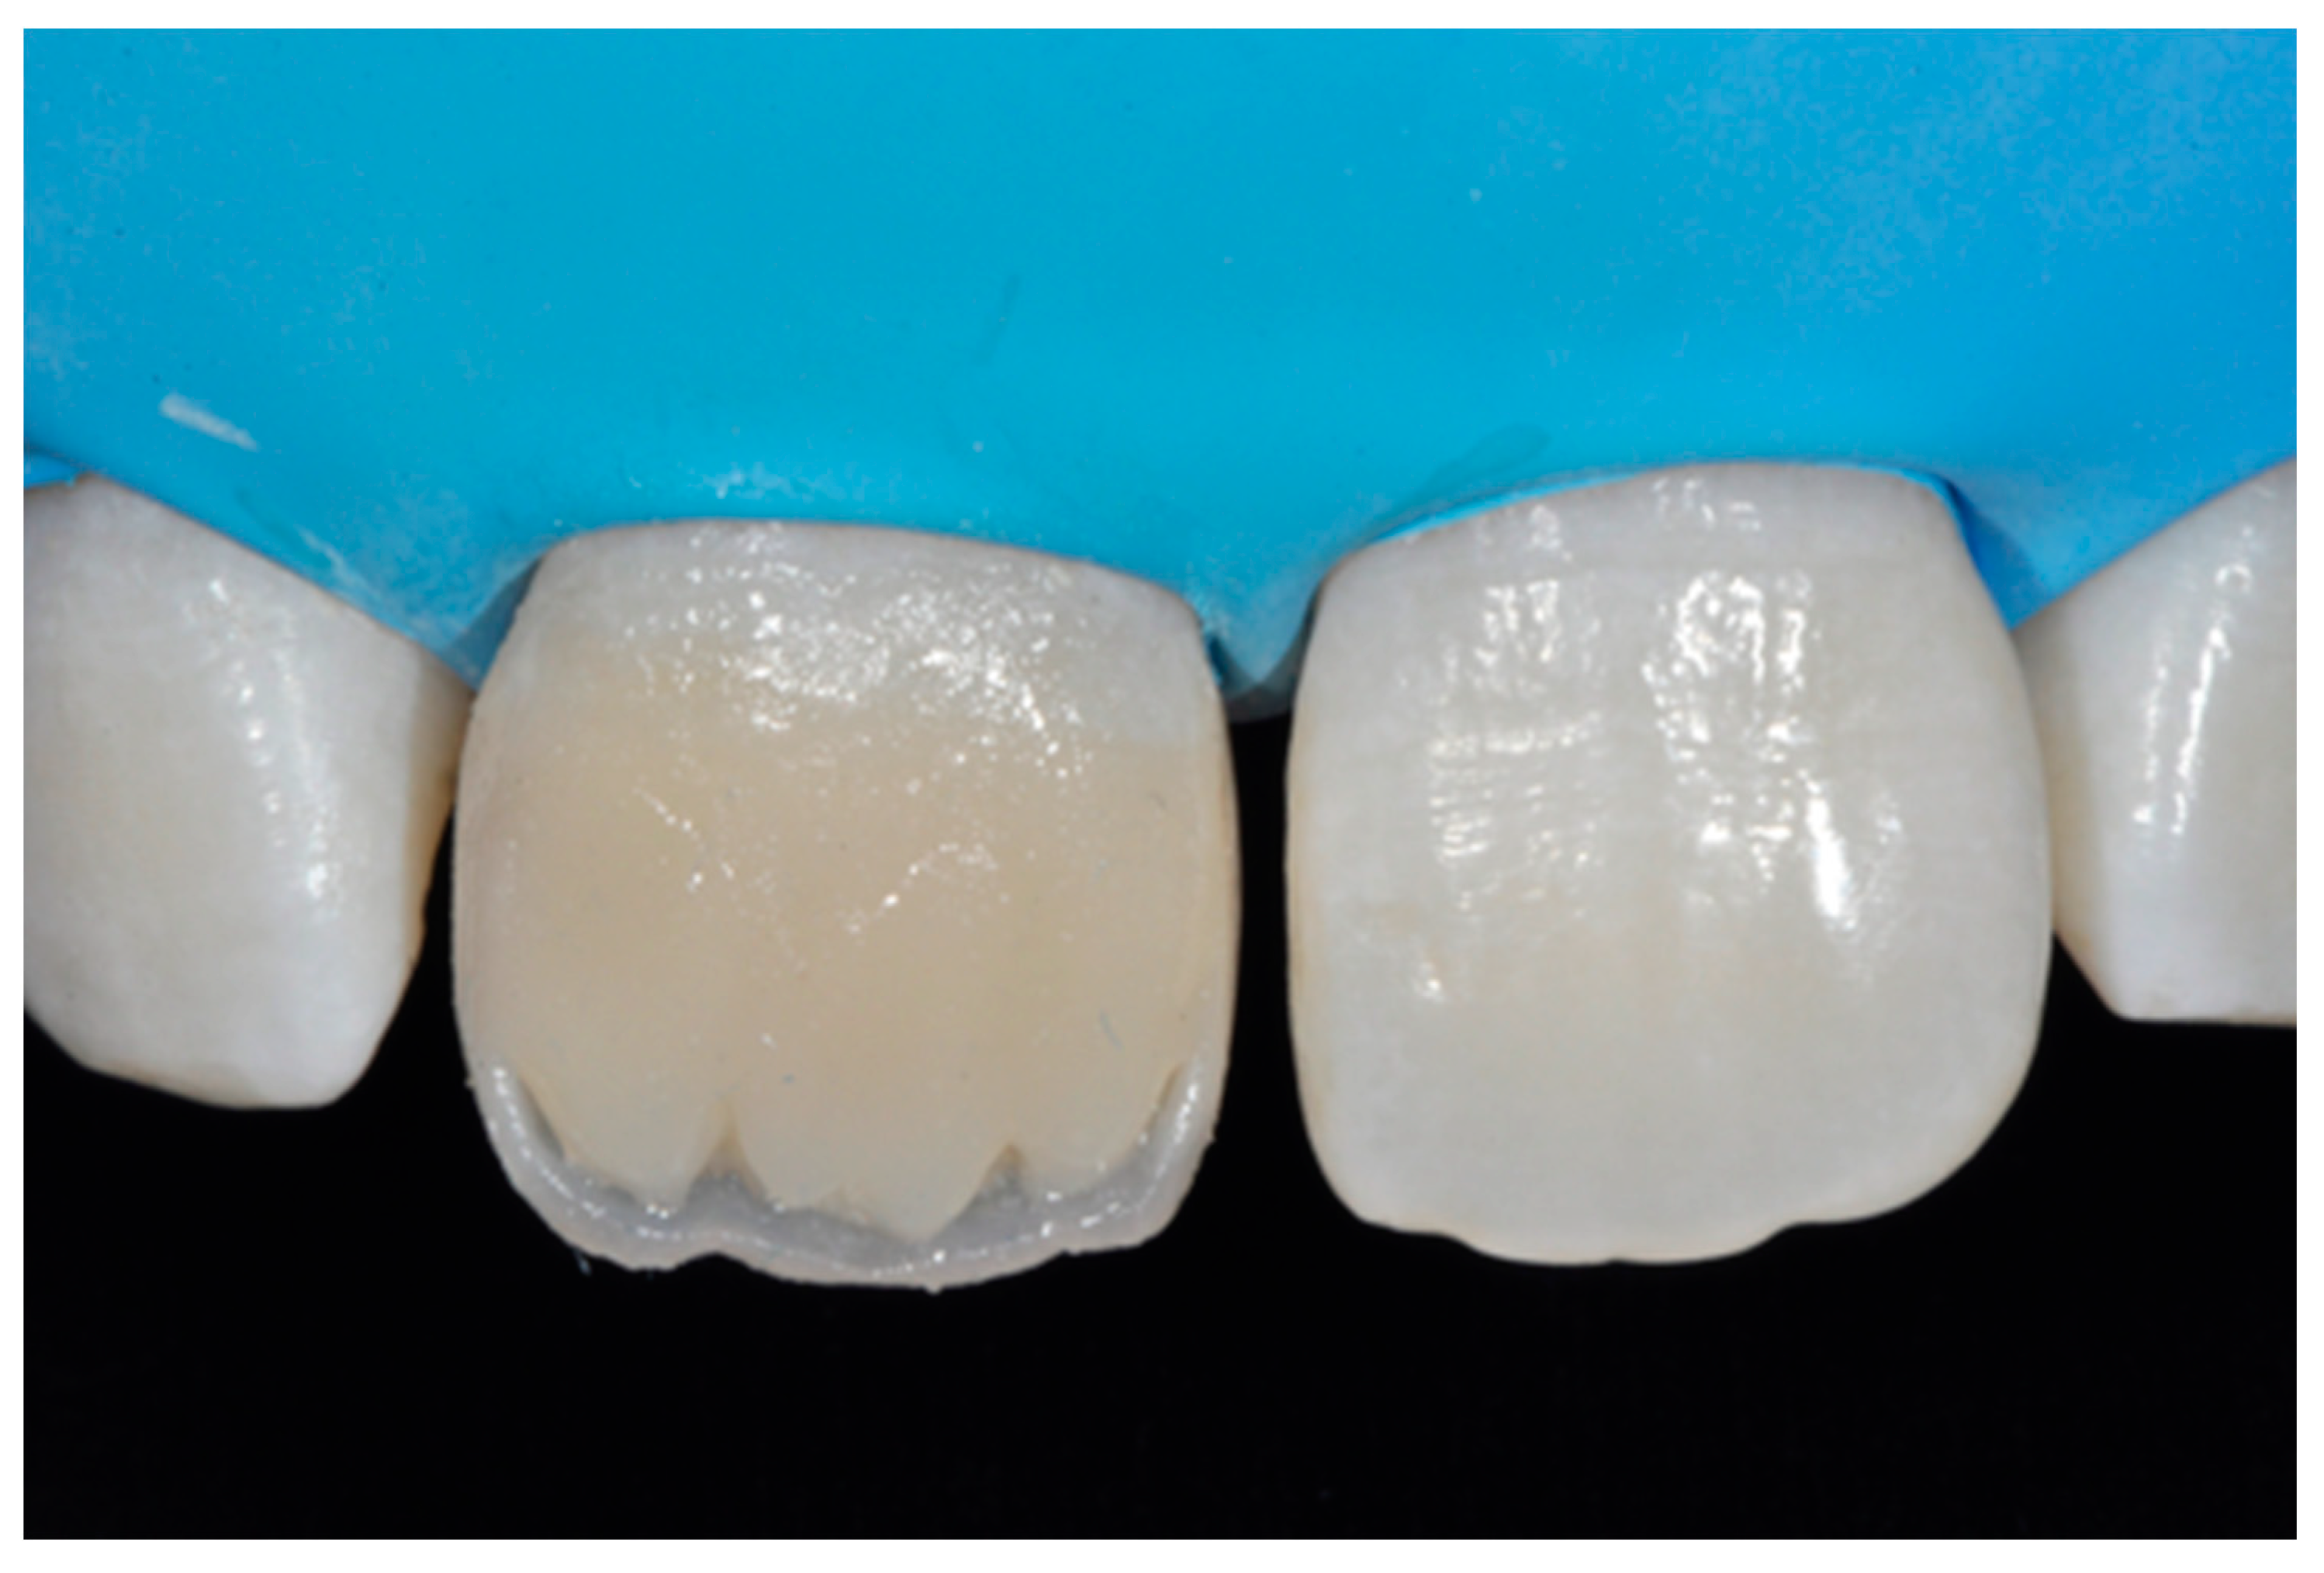

2.1.3. Completion of the Layering Procedure, Finishing and Polishing

A single shade of dentin (Clearfil Majesty ES-2, A1D, Kuraray Noritake Dental, Tokyo, Japan) was then applied placing separate increments (Figure 10 and Figure 11) to build the dentinal body, leaving space for incisal translucencies. The translucent shade (Clearfil Majesty ES-2, A1E, Kuraray Noritake Dental, Tokyo, Japan) was then applied to complete the restoration (Figure 12).

Figure 12.

Enamel layer applied. Reprinted from Restauri diretti nei settori anteriori, G. Paolone, S. Scolavino, © 2021, with permission from Quintessence Publishing Italy.